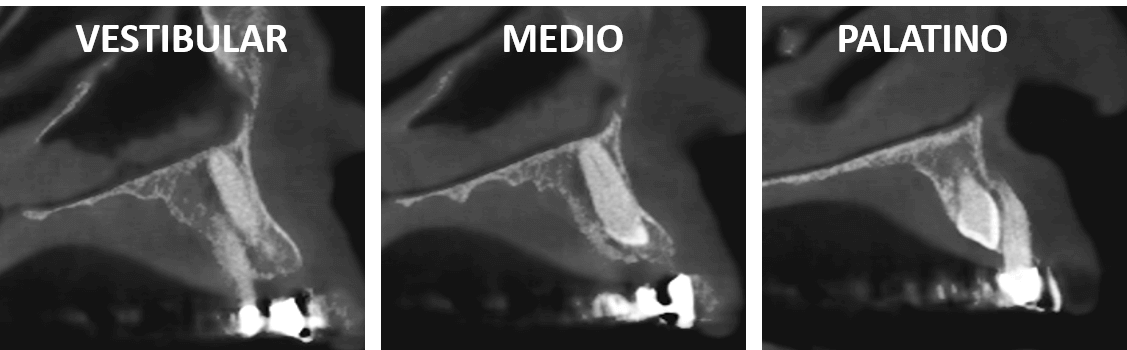

Fig.2

En cortes sagitales (Fig.2) se observa en el corte vestibular del órgano dentario 13 la proximidad del ápice radicular con el piso de las fosas nasales; en el corte medio se observa la proximidad del tercio medio y cervical radicular con la tabla ósea vestibular y en el corte palatino se observa la relación de la corona del canino con la raíz del órgano dentario 12.